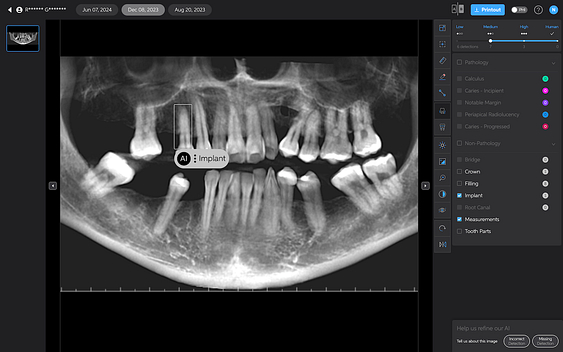

Pearl currently only analyzes 2D radiographs, including intraoral radiographs and OPGs. 3D X-ray analysis is under development and is scheduled for release later in 2025.

Second Opinion aims to assist dental professionals in identifying a range of dental conditions by automatically highlighting areas of potential concern. However, it's crucial to remember that the accuracy of AI detections can vary, and dental professionals must be able to evaluate these suggestions critically.

Pearl’s Second Opinion can report on six conditions on 2D x-rays at this stage. Let's go over each one of the AI detections below:

Here are some things I noticed AI missed or picked up incorrectly:

- It detects a ‘notable margin’ on an implant crown that is just the abutment-crown joint.

- Or calls a natural tooth an implant

- Or misses the apparent secondary decay under a PFM

- Seems to be less sensitive to widening of the PDL, rarely picking it up.

- It denoted leftover resin cement around a crown as calculus

- Does not seem to pick up resorbed roots

But overall, it is still impressive. Of course, AI does not have ‘bad days’, tiredness, or fatigue. It reports things the same way each time. It also gets better with time, one would hope.